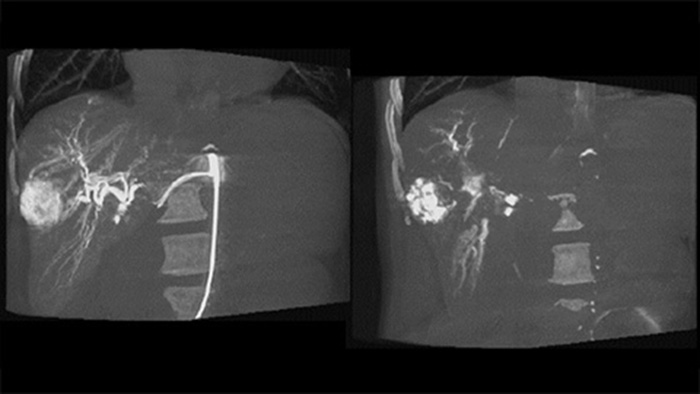

Fusion d’images 3D avant et après embolisation avec double affichage

La fonction double affichage permet la visualisation simultanée de l’image 3D de la phase artérielle avant embolisation et de l’image après embolisation pour évaluer la fin du traitement.